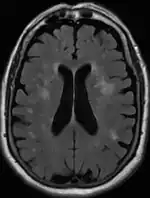

Axial T2 FLAIR sequence MR image of a middle-aged man with leukoaraiosis.

Leukoaraiosis is a particular abnormal change in appearance of white matter near the lateral ventricles. It is often seen in aged individuals, but sometimes in young adults.[1][2] On MRI, leukoaraiosis changes appear as white matter hyperintensities (WMHs) in T2 FLAIR images.[3][4] On CT scans, leukoaraiosis appears as hypodense periventricular white-matter lesions.[5]

These white matter changes are also commonly referred to as periventricular white matter disease, or white matter hyperintensities (WMH), due to their bright white appearance on T2 MRI scans. Many patients can have leukoaraiosis without any associated clinical abnormality. However, underlying vascular mechanisms are suspected to be the cause of the imaging findings. Hypertension, smoking, diabetes,[3] hyperhomocysteinemia, and heart diseases are all risk factors for leukoaraiosis.